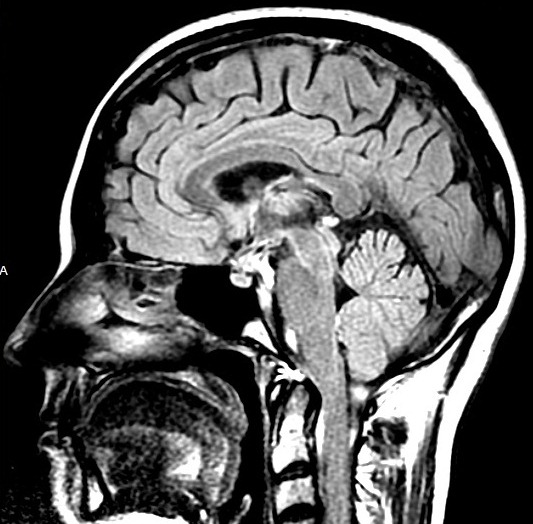

A ressonância magnética tem condições de diagnosticar vários tipos de lesões causadas pelo álcool no cérebro dos indivíduos, sendo algumas reversíveis e outras permanentes.

O consumo crônico de álcool resulta na redução e atrofia de partes específicas do cérebro que podem levar à alteração do equilíbrio e marcha, dificuldade de raciocínio, cálculo e memória, danos muitas vezes progressivos e irreversíveis, além de quadros graves que evoluem para coma e morte se não forem tratados com rapidez e eficiência.

As regiões do cérebro mais afetadas pelo consumo excessivo de álcool são responsáveis por alterações na memória e no comportamento, deficiência cognitiva, dificuldade para articular palavras e movimentos.